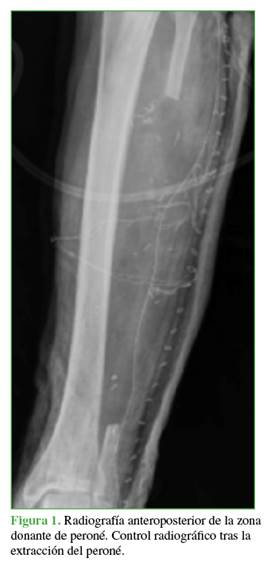

El tiempo medio hasta la consolidación radiográfica completa fue de 7.16 meses (desviación estándar [DE] ± 0,75) (Figura 3). El tiempo medio hasta la consolidación fue más prolongado en el miembro superior (8 meses, DE ± 3) que en el miembro inferior (7 meses, DE ± 0,70). El tiempo medio hasta el inicio de la carga en los pacientes operados en el miembro inferior fue de 4.1 ± 1.47 meses.

El paciente con consolidación viciosa en varo fue sometido al año a una osteotomía correctora valguizante tibial proximal y fijación con placa atornillada (Figura 4). La fractura patológica se produjo a los tres años de la operación inicial de CVP y fue tratada con reducción abierta, autoinjerto de hueso y una placa de carbono.